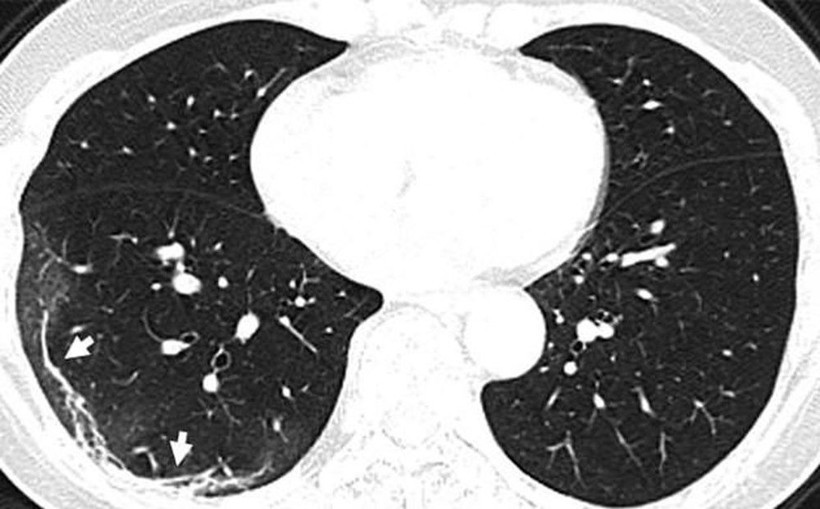

Diğer taraftan, A görüntüsüyle F görüntüsü karşılaştırıldığında, akciğer uzuvlarında bulunan sıvının, zaman içinde belirgin bir şekilde corona virüs nedeniyle arttığı görülebiliyor. Röntgenleri paylaşılan adamın yaklaşık iki hafta boyunca ateş ve öksürük belirtileri göstermesinin ardından 25 Aralık 2019'da hastaneye kaldırıldığı bir hafta sonra ise hayatını kaybettiği açıklandı.

Wuhan'a seyahat ettikten sonra corona virüse yakalanan 54 yaşında bir kadının bilgisayarlı tomografi taramaları da akciğerlerinde hava boşluklarının kısmen dolduğunu gösteriyor. Solda yer alan fotoğrafta kırmızı olarak görülen alanlarda nodüller, sağ tarafta ise akciğer ve trakeanın üç boyutlu görüntüsü yer alıyor. Beyaz alanlarda corona virüsün tahribi görülüyor.